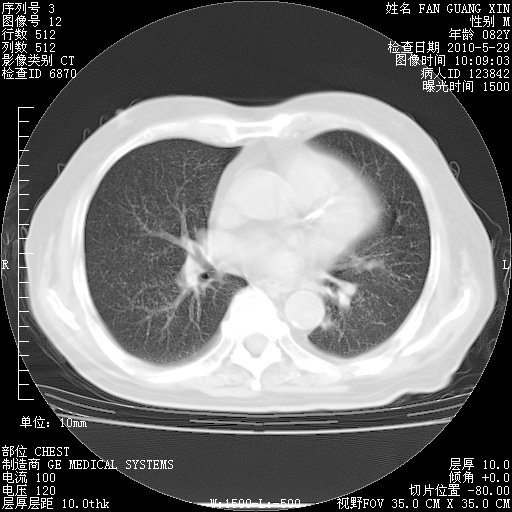

再治疗10天后的肺部CT

从白细胞总数和中性比例看好像合并感染。肺部纹理好像比上次多,支气管炎?其他感染?

阅读此次胸部CT,肺间质渗出性改变较入院时有吸收。目前从体温、白细胞、中性分叶明显增高,肯定存在细菌感染(发生医院感染哦,若无消化道及泌尿系统等感染的依据,肺部感染可能大)。若你院头孢哌酮舒巴坦钠耐药率较高,同意你的方案,若48小时体温仍高,可考虑使用碳青霉稀类抗菌药物,同时可予超声雾化、注意滴数时加大液体量。白蛋白33.30g/L较低哦,需加强营养等支持治疗。